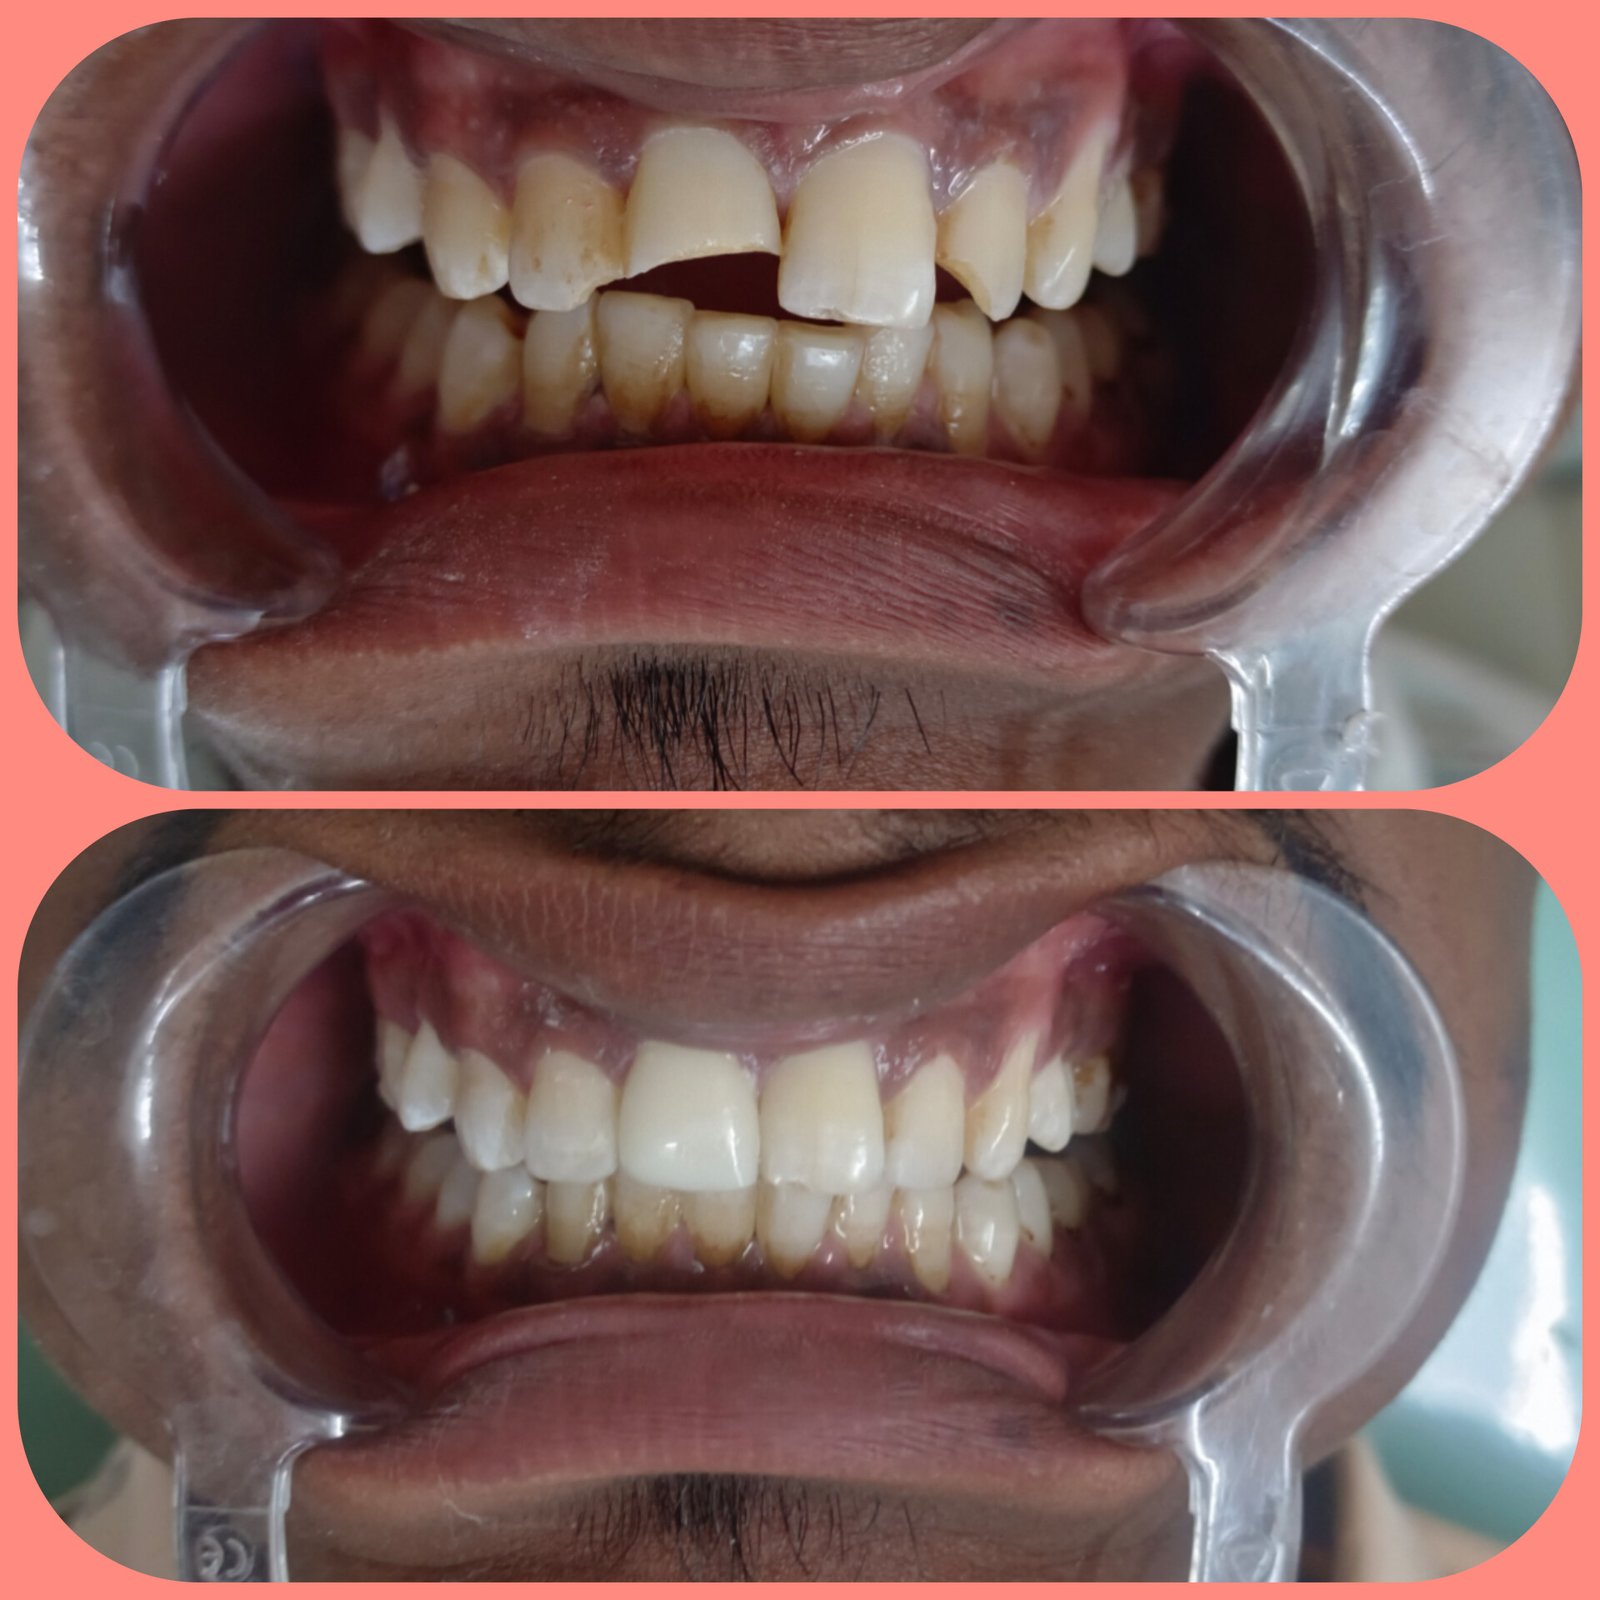

ЁЯПе рдзрд╛рд░рд╛рд╢рд┐рд╡ рдЬрд┐рд▓реНрд╣реНрдпрд╛рддреАрд▓ рдкреНрд░рд╕рд┐рджреНрдз рдбреЗрдВрдЯрд▓ рд╣реЙрд╕реНрдкрд┐рдЯрд▓ & рдлреЗрд╢рд┐рдпрд▓ рдЯреНрд░реЙрдорд╛ рдХреЗрдЕрд░ рд╡ рдЗрдореНрдкреНрд▓рд╛рдВрдЯ рд╕реЗрдВрдЯрд░ ЁЯПе ЁЯПердЕрддреНрдпрд╛рдзреБрдирд┐рдХ рдбрд┐рдЬрд┐рдЯрд▓ рдПрдХреНрд╕-рд░реЗ ЁЯПердЗрдВрдЯреНрд░рд╛ рдУрд░рд▓ рдХреЕрдореЗрд░рд╛ рджреНрд╡рд╛рд░реЗ рддрдкрд╛рд╕рдгреА ЁЯж╖рдЕрд▓реНрдЯреНрд░рд╛рд╕реЛрдирд┐рдХ рдорд╢реАрдирджреНрд╡рд╛рд░реЗ рджрд╛рдд рд╕рд╛рдл рдХрд░рдгреЗ ЁЯж╖рдХреГрддреНрд░рд┐рдо рджрдВрддрд░реЛрдкрдг ЁЯж╖рдЕрдХреНрдХрд▓рджрд╛рдбреЗ рд╡рд░реАрд▓ рд╢рд╕реНрддреНрд░рдХреНрд░рд┐рдпрд╛ ЁЯж╖рдЬрдмрдбреНрдпрд╛рдВрдЪреЗ рдлреНрд░реЕрдХреНрдЪрд░ рд╡рд░реАрд▓ рд╢рд╕реНрддреНрд░рдХреНрд░рд┐рдпрд╛ ЁЯзмрдЕрддреНрдпрд╛рдзреБрдирд┐рдХ рдкрджреНрдзрддреАрдиреЗ рджрд╛рддрд╛рдВрдЪреНрдпрд╛ рдирд╕рд╛ рд╡рд░реАрд▓ рдЙрдкрдЪрд╛рд░ ЁЯзмрддреЛрдВрдбрд╛рддреАрд▓ рдореМрдЦрд┐рдХ рд╢рд╕реНрддреНрд░рдХреНрд░рд┐рдпрд╛ ЁЯзмрд╕рдВрдкреВрд░реНрдг рдХрд┐рдВрд╡рд╛ рдЕрдВрд╢рддрдГ рдХрд╡рд│реА рдмрд╕рд╡рдгреЗ ЁЯзмрд╡реЗрдбреЗрд╡рд╛рдХрдбреЗ рджрд╛рдд рд╕рд░рд│ рдХрд░рдгреЗ

ЁЯПе рдЕрддреНрдпрд╛рдзреБрдирд┐рдХ рдкрджреНрдзрддреАрдиреЗ рджрдВрдд рд░реЛрдЧрд╛рд╡рд░реАрд▓ рд╕рд░реНрд╡ рдЙрдкрдЪрд╛рд░ рдЙрдкрд▓рдмреНрдз

ЁЯПе рд╕реНрдХреНрд░реВ рдЪреНрдпрд╛ рд╕рд╛рд╣реНрдпрд╛рдиреЗ рдлрд┐рдХреНрд╕ рджрд╛рдд рдмрд╕рд╡рдгреЗ